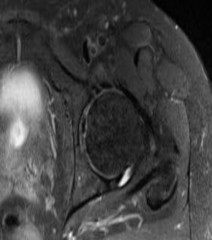

A 55-year-old carpenter presents with right shoulder pain and weakness after attempting to lift a heavy tool box. On physical examination, he demonstrates a positive drop-arm test and profound weakness with active abduction in the scapular plane. An MRI confirms a massive, retracted tear of the supraspinatus and infraspinatus tendons. Fatty infiltration of these muscles is graded. Which classification system is most commonly used to grade fatty infiltration of the rotator cuff muscles on imaging?

The Goutallier classification is used to quantify the amount of fatty infiltration of the rotator cuff muscles, originally described on CT but now widely adapted for MRI. High grades of fatty infiltration (Goutallier 3 and 4) are associated with poor functional outcomes and higher re-tear rates following surgical repair.